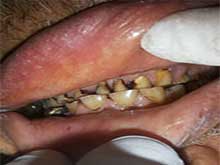

Full Mouth Zirconia (All-Ceramics)

Case 2